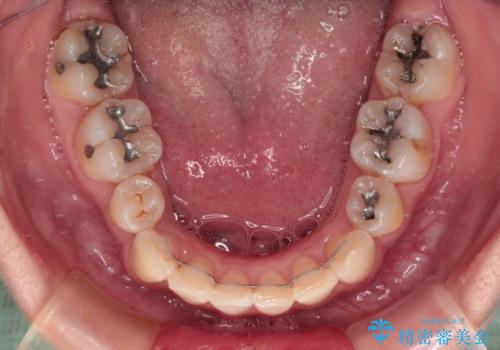

- 治療期間

- 3年1ヶ月

- 内側に倒れ込んだ歯や下の前歯が隠れてしまうほどの咬み合わせを改善したいとのことで来院された患者様です。

下顎の叢生を解消するために抜歯が必要であり、奥歯の咬み合わせや口元の印象から、上顎も同様に抜歯と判断し、上下左右の第1小臼歯4本抜歯してワイヤー装置にて矯正治療を行うこととしました。